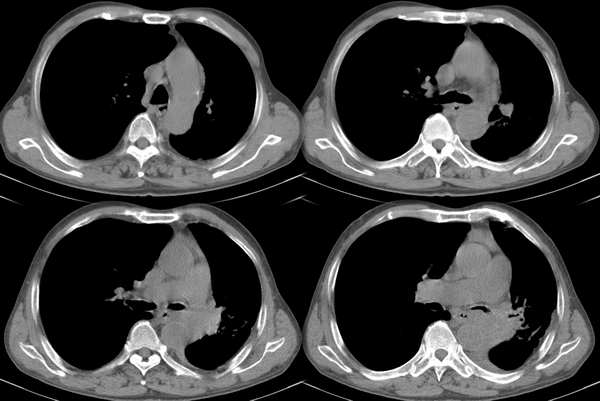

m67y外院ct诊断肺ca,现来我科复查ct

左肺下叶支气管狭窄局部见肿块影左肺下叶不张,肺癌应该没问题吧

左主支气管变窄,左下叶部分不张,考虑肺癌可能性大

考虑左下肺中央型肺癌并肺不张,建议支气管镜检查。

左下肺中央型肺癌并不张可能性大,为慎重起见,请楼主提供病史,以排除支气管内膜结核引起肺不张。

左中央型肺癌并左下叶肺不张,建议纤支镜检查.